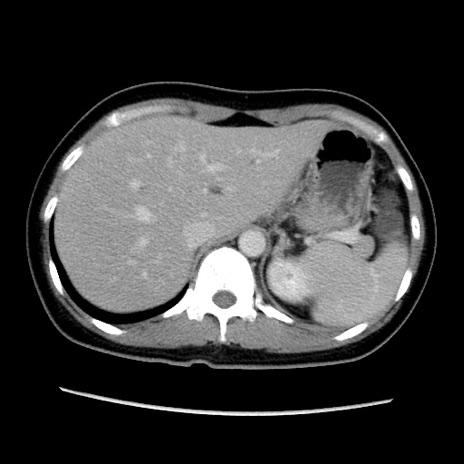

症例39(横断像)

【症例】40歳代女性

【主訴】上下腹部痛

【現病歴】2日目から下腹部痛あり。夜間は痛みで眠れなかった。昨日より上腹部痛と下痢が出現。臥位で痛みは軽快したため、休んでいた。本日になって臥位でも立位でも痛みが強くなってきたため救急要請。

【既往歴】子宮内膜症

【身体所見】部:平坦・軟、左上下腹部に圧痛あり、反跳痛あり。

【データ】WBC 21800、CRP 26.78